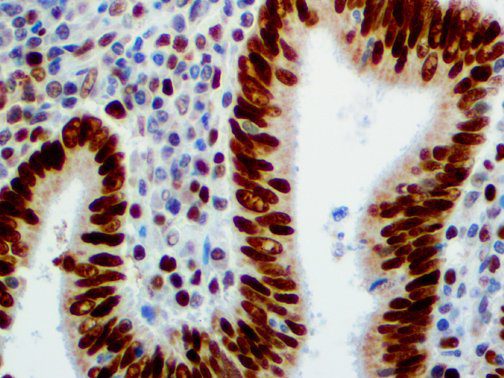

The first cytokines released are interleukin 1β (IL-1β) and tumor necrosis factor-α (TNF-α), which attract a variety of circulating white blood cells (WBCs) to the infection site, including neutrophils, monocytes, macrophages, and natural killer (NK) cells. This response, along with the antipathogenic chemicals released by these cells (i.e., complement), comprise the innate immune response. These cells directly attack the invading pathogen and also release additional cytokines, chief among them interleukin-1 and 6 (IL-6). IL-6 is essential for invoking the adaptive immune response, which calls T-cells, B-cells, and T helper (Th) cells to the infection site. IL-6 also stimulates further recruitment, proliferation and activation of macrophages.

It is the ICU physician who is most likely to witness one of the deadliest manifestations of the abnormal immunological response, the cytokine storm syndrome (CSS). This response is also referred to by some as the cytokine release syndrome (CRS). CSS is characterized by continuous activation and expansion of macrophage and lymphocyte populations, which secrete large amounts of cytokines, causing the cytokine storm. This massive cytokine release is akin to hemophagocytic lymphohistiocytosis (HLH) disease, a syndrome characterized by initial unchecked and persistent activation of cytotoxic T lymphocytes and NK cells.